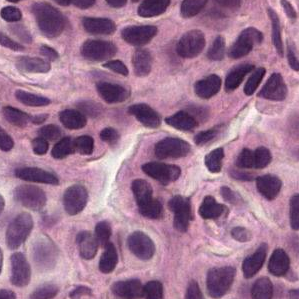

Given a gigapixel pathology image (slide111Each slide contains human lymph node tissue stained with hematoxylin and eosin (H&E), and is scanned at the most common high magnification in a microscope, “40X”. We also experimented with 2- and 4-times down-sampled patches (“20X” and “10X”).), the goal is to classify if the image contains tumor and localize the tumors for a pathologist’s review. This use case and the difficulty of pixel-accurate annotation (Fig. 3) renders detection and localization more important than pixel-level segmentation. Because of the large size of the slide and the limited number of slides (), we train models using smaller image patches extracted from the slide (Fig. 1). Similarly, we perform inference over patches in a sliding window across the slide, generating a tumor probability heatmap. For each slide, we report the maximum value in the heatmap as the slide-level tumor prediction.

We utilize the Inception (V3) architecture [20] with inputs sized (the default) to assess the value of initializing from existing models pre-trained on another domain. For each input patch, we predict the label of the center region. A 128 pixel region can span several tumor cells and was also used in [16]. We label a patch as tumor if at least one pixel in the center region is annotated as tumor. We explored the influence of the number of parameters by reducing the number of filters per layer while keeping the number of layers constant (e.g., in TensorFlow). We denote these models “small”. We also experimented with multi-scale approaches that utilize patches at multiple magnifications centered on the same region (Fig. 3). Because preliminary experiments did not show a benefit from using up to four magnifications, we present results only for up to two magnifications.

Datasets Our work utilizes the Camelyon16 dataset [1], which contains 400 slides: 270 slides with pixel-level annotations, and 130 unlabeled slides as a test set.333The test slides labels were released recently as part of the training dataset for Camelyon17. We used these labels for evaluation, but not for parameter tuning. We split the 270 slides into train and validation sets (Appendix) for hyperparameter tuning. Typically only a small portion of a slide contains biological tissue of interest, with background and fat comprising the remainder (e.g., Fig. 3). To reduce computation, we removed background patches (gray value [12]), and verified visually that lymph node tissue was not discarded.

Figures 1 and 3 highlight the variability in the images. Although the current leading approaches report improvements from color normalization, our experiments revealed no benefit (Appendix). This could be explained by our extensive data augmentations causing our models to learn color-invariant features.

0.A.3 Image Color Normalization

As can be seen in Fig. 1 & 3, the (H&E) stained tissue vary significantly in color. These variations arise from differences in the underlying biological tissue, physical and chemical preparation of the slide, and scanner adjustments. Because reducing these variations have improved performances in other automated detection systems [4, 13], we experimented with a similar color normalizing approach. However, we have not found this normalization to improve performance, and thus we detail our approach for reference only. This lack of improvement likely stems from our extensive color perturbations encouraging our models to learn color-insensitive features, and thus the color normalization was unnecessary.